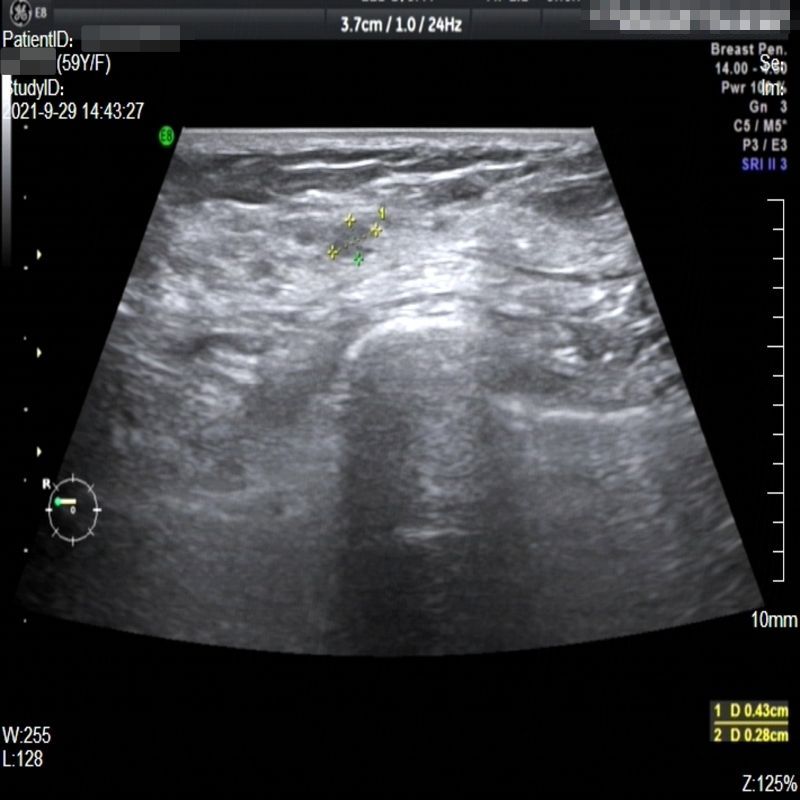

Images with certain annotations are considered noisy images in the context of the noise removal task, and corresponding images without these annotations are considered clean. Some typical images with various annotation are provided in Fig. 1.

In essence, a body marker annotation is a marker selected from a fixed set of icons that indicates different regions of the human body and its current orientation. It is typically located at the edge of the ultrasnoic image area and is labeled by the sonographer. On some ultrasound machines, the body marker annotation has a fixed position.

The radial line annotation is pairs of connected cross markers. They are usually placed at the edge of the lesion area, with its placement determined by the size of the lesion. One to three pairs of cross markers may be present in an image, corresponding to the three axes of 3D space, but typically there are only two pairs.

The vascular flow annotation is not an additional labeling feature meant to simplify identification. Rather, it serves as a bounding box that identifies the specific area of the image being examined by the ultrasound flowmeter. However, to keep things simple, we will continue to call it a form of annotation. The presence of this annotation indicates that the relevant examination has been conducted.

Refer to caption

(a)

(b)

(c)

Figure 1: Images with various annotations. (a) body marker annotation, (b) radical line annotation, (c) vascular flow annotation.